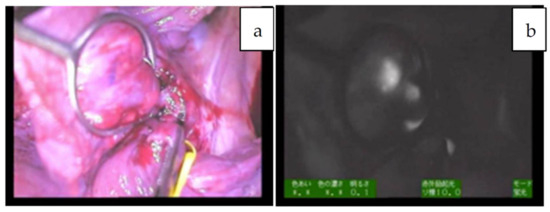

| 5 | 15 | 7y/M | PDE neo system | Resection for peritoneal nodules | NA | diffuse | 21 × 14 × 18 mm | 525.6 | identification, tumor margin, not disease free |

| 6 | 20 | 19y/F | Pinpoint + PDE neo | Pleural and diaphragm resection | wholly epithelial type and fetal subtype | diffuse | 47 × 38 × 21 mm | 2885 | tumor margin, identification, 28 m |